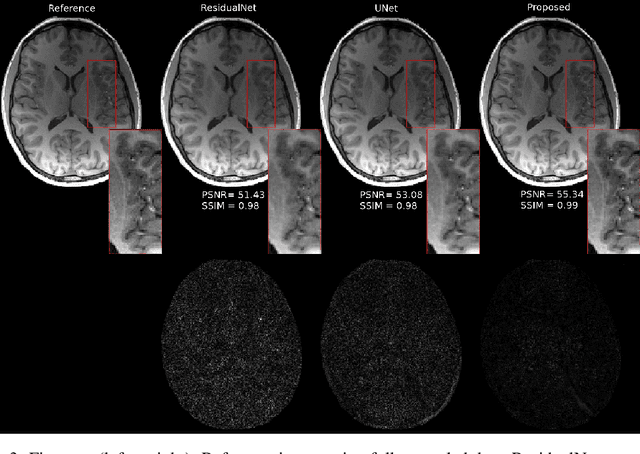

Abstract:Fast data acquisition in Magnetic Resonance Imaging (MRI) is vastly in demand and scan time directly depends on the number of acquired k-space samples. The data-driven methods based on deep neural networks have resulted in promising improvements, compared to the conventional methods, in image reconstruction algorithms. The connection between deep neural network and Ordinary Differential Equation (ODE) has been observed and studied recently. The studies show that different residual networks can be interpreted as Euler discretization of an ODE. In this paper, we propose an ODE-based deep network for MRI reconstruction to enable the rapid acquisition of MR images with improved image quality. Our results with undersampled data demonstrate that our method can deliver higher quality images in comparison to the reconstruction methods based on the standard UNet network and Residual network.